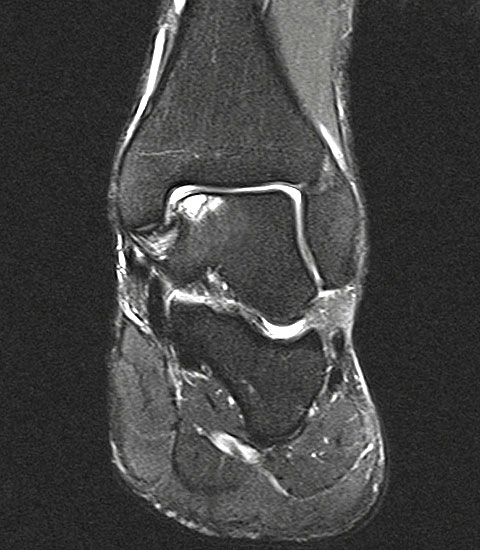

Abbildung 1: Osteochondrale Läsion der medialen Talusschulter mit subchondralem Begleitödem und Zyste.

Abbildung 1

• MRT des Sprunggelenks zur Beurteilung der Knorpelläsion, möglichen subchondralen Zysten, nekrotischen Knochenarealen und anderen Begleitpathologien (Abbildung 1).

Abbildung 18: MRT 12 Monate nach Implantation einer AMIC Membran an der medialen Talusschulter. Das Knochenödem ist fast vollständig abgeklungen bei vollständiger Abdeckung der Defektzone.

Abbildung 18